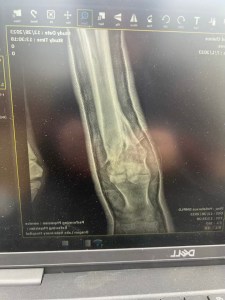

While traditional equine medical care might see injuries like hers as insurmountable, this filly’s tenacious spirit was a testament to an animal’s engrained will to survive. By the time she was discovered with her injury, she was facing:

- A severe and rapidly-spreading infection.

- A complex fracture of her cannon bone with severe soft tissue damage.

On day one under the surgeons care it was determined the little foals leg could likely be saved. The next 3 months in Cody, Wyoming were touch and go as the team at Yellowstone Equine Hospital controlled the infection and set Second Chance’s bones to fuse. It was a miracle in and of itself, but that was only the beginning. The rest of Second Chance’s healing journey was dependent on the care she would receive post Yellowstone. Now she needed to come home and settle in to beat the harsh Canadian winter.

You and your family willingness to fight as long as Second Chance will to continued fighting. The xrays tell the store, the truth. Most would have ended it all. To spend the time making phone calls, asking questions, then traveling for days to safely transport her and her mom to Wyoming. Vet’s that were also willing to take on the challenge. Above and beyond, I am not sure you know any other way, to be honest. Second Chance looks unbelievable beautiful, strong and even after all that she has been through you can still see the fight in her sweet soft eyes. When you are around her…. she know you are her Hero and she shows you her love in her behavior around you.